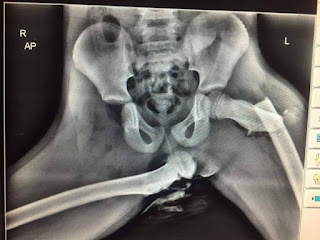

Shared by Autoblog, a young woman has suffered “life changing” injuries when she sat with her feet up. When the car she was riding in got caught in a minor accident, the result to her is rather gruesome. Basically, her foot flew into her face, breaking her nose, femur, and ankle. In her x-rays, the doctors discovered that one femur snapped, while one hip is broken in the socket, and the other has been dislocated.

If you want visual proof, check out her x-ray:

It must be remembered that airbags deploy anywhere between 177 km/h to 354 km/h. If you ride with your feet on the dash, and you’re involved in an accident, the force of the impact is enough to send your knees through your eye sockets.

Always remember: for the airbags to work, sit up straight with your feet on the floor.